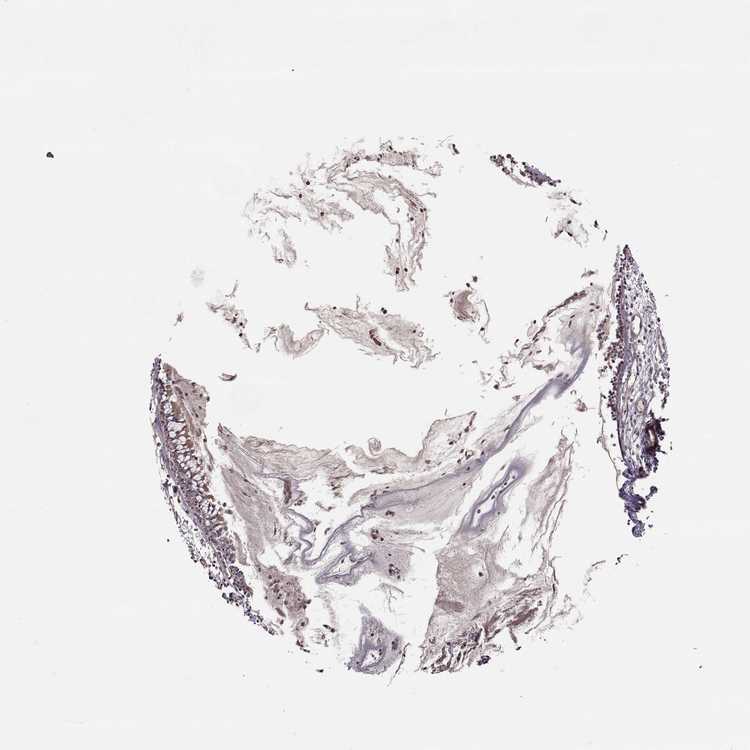

NASOPHARYNX - Antibody stainingi

Antibody staining in the annotated cell types in the current human tissue is reported as not detected, low, medium, or high, based on conventional immunohistochemistry profiling in selected tissues. This score is based on the combination of the staining intensity and fraction of stained cells.

Each image is clickable and will lead to virtual microscopy that enables deeper exploration of all samples and also displays staining intensity scores, fraction scores and subcellular localization as well as patient and tissue information for each sample.

Antibody HPA066697

Respiratory epithelial cells Low